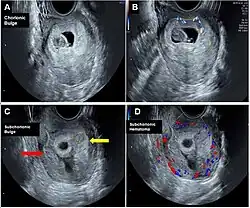

Chorionic bump

| Chorionic bump | |

| Other names | chorionic bulge |

Chorionic bump is a rare medical condition defined as an irregular, convex bulge or protrusion from the choriodecidual surface into the gestational sac.[1][2] It is medically defined as a separate entity from a chorionic hematoma.[3]

Identification of a chorionic bump in early first trimester pregnancy represents a significant risk factor for pregnancy loss, given a live birth rate of less than 50%.[4] The incidence rate for chorionic bump is estimated to be between 1.5 and 7 per 1000 pregnancies.[3]